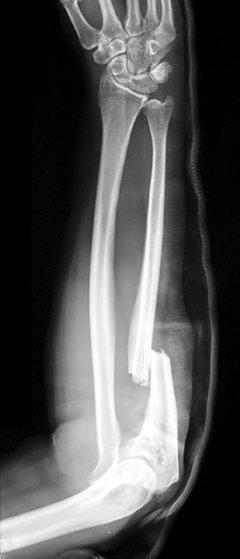

Monteggia's fractures

Definition: these are fractures of the proximal third (usually) of the ulna with associated dislocation of the radial head. Classified as:

Type I - fracture with anterior radial head dislocation. This is the most common (60%).12

Type II - fracture of the proximal ulna with posterior or posterolateral dislocation of the radial head (15%).12

Type III - fracture of the ulnar metaphysis with lateral or anterolateral dislocation of the radial head (20%).12

Type IV - fracture of both the radius and ulna at their proximal third with anterior dislocation of the radial head (5%).12

Mechanism of injury: usually caused by a fall on to an outstretched, extended and pronated elbow, or by a direct blow.

Presentation: acute, severe pain and swelling in the forearm and elbow. Damage may occur to the posterior interosseous nerve.

Monteggia fracture

© Jane Agnes (own work), via Wikimedia Commons

By Jane Agnes (own work), via Wikimedia CommonsInvestigation: X-ray the entire length of the radius and ulna, including the wrist and elbow - AP and lateral views are usually sufficient but there may be a need for radiocapitellar views.

Management: in adults, immobilise the joint in a splint and refer for open reduction and internal fixation. Most paediatric Monteggia's fractures are treated closed.13

Isolated proximal ulnar fractures are rare. Always examine for a Monteggia's fracture/dislocation.